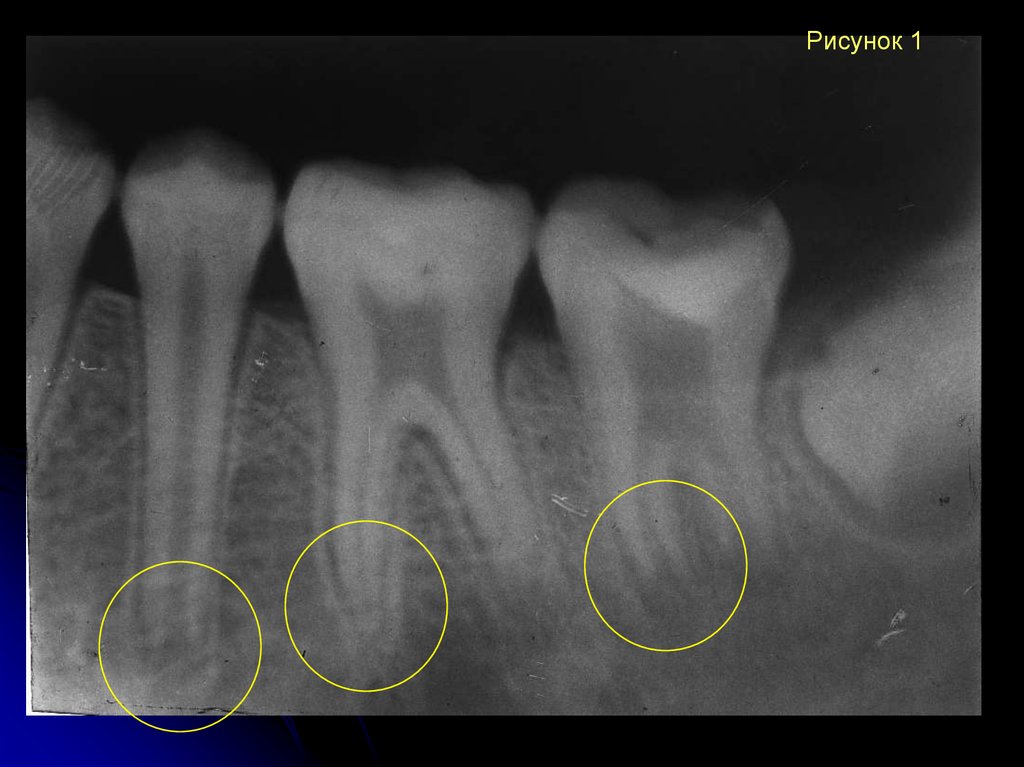

Рентгеновские снимки кариеса корня зуба

Раздел: Визуальные уроки